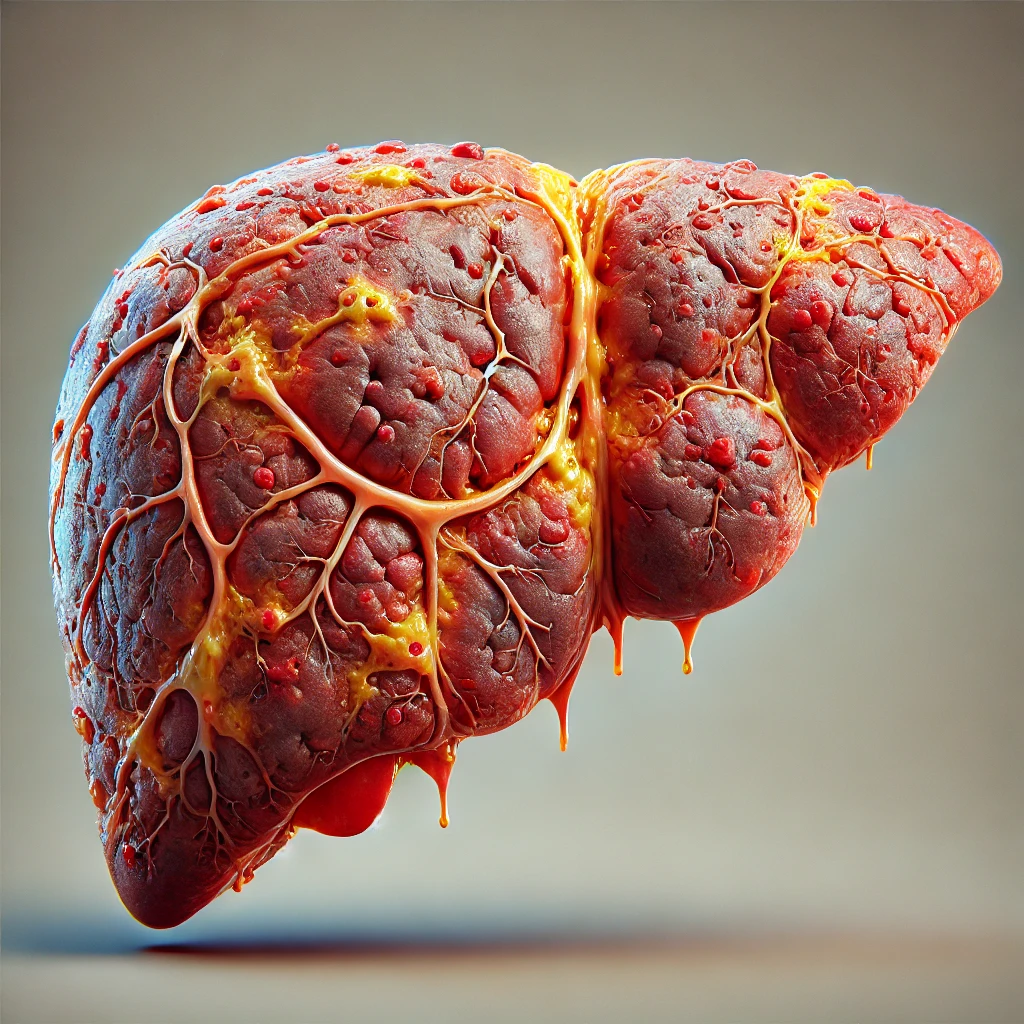

Ele é capaz de tratar completamente as principais doenças que podem atingir seu fígado, a (DHGA) Doença Hepática Gordurosa Alcóolica, (DHNGA) Doença Hepática Gordurosa não Alcóolica.

O acúmulo de gordura no fígado está diretamente ligado aos hábitos do dia a dia e à sobrecarga metabólica do organismo, podendo causar:

É um desequilíbrio metabólico que afeta sua saúde física e sua qualidade de vida.

Ajuda a restaurar a função hepática, recuperar níveis de energia da juventude e derreter anos de gordura abdominal!

Figdetox age restaurando as celulas do Fígado, fazendo com que seu figado volte a funcionar normal, eliminando a gordura e se auto regenerando.